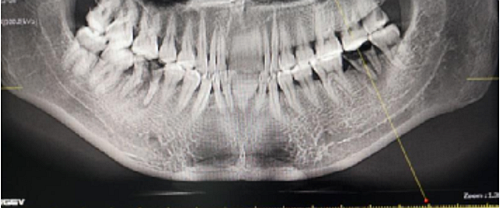

左側(cè)下頜第二磨牙及右側(cè)下頜第一磨牙同時(shí)即刻種植病例?;颊吣贻p女性,無系統(tǒng)性疾病。37及46殘冠及殘根,且46劈裂,無法冠修復(fù),必須拔除。37根尖慢性炎癥,大量肉芽組織存在,46根分叉較高,根分叉骨質(zhì)尚可。CBCT示:根尖骨質(zhì)至下牙槽神經(jīng)管距離可滿足種植體的初期穩(wěn)定性,遂考慮即刻種植,并在種植體周邊填入骨粉并覆蓋骨膜,雙側(cè)的種植體初期穩(wěn)定性相差無幾,但考慮到37根尖慢性炎癥較大,遂給予埋入式種植。